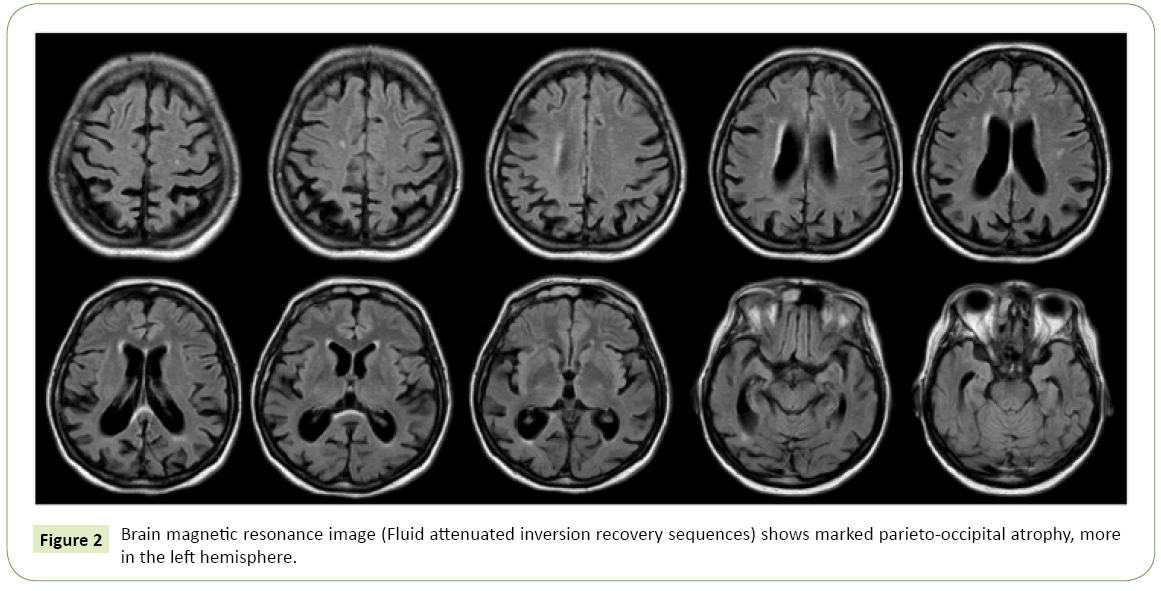

Belangrijk: alleen een scan (meestal een MRI) kan aantonen of er sprake is van corticale atrofie. En nog belangrijker: een scan is maar een onderdeel van het hele verhaal. Artsen kijken naar veel meer dan alleen die scan. Dus raak niet in paniek als je ergens leest over "atrofie"! Laat de experts hun werk doen.